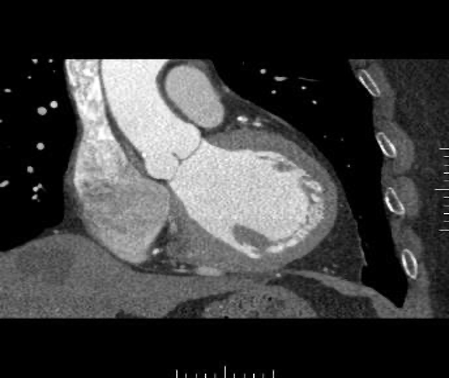

Example of a sufficiently good examination. Good contrast in the coronary arteries. The heart is displayed without steps.

Another example after 3D post-processing (obligatory vessel and volume display): The coronary vessels are clearly and continuously displayed. Image source: Rolf et al. 2023